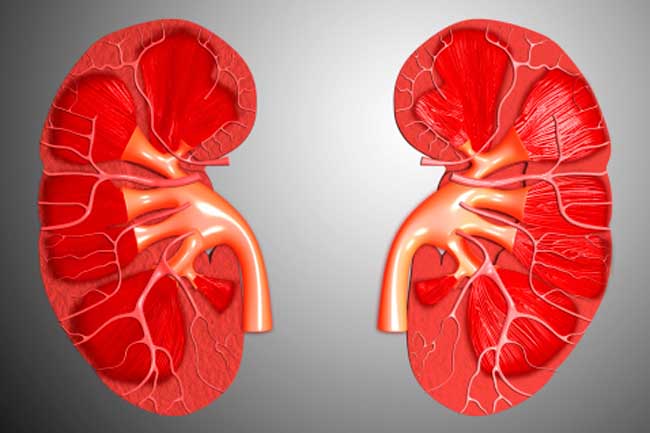

Detecting kidney disease early is vital-it can slow its progression, prevent complications, and potentially reverse end-stage kidney failure. By adopting healthier habits now, you can significantly lower your risk and reduce the chances of developing kidney disease.

Adopting healthier lifestyle choices and dietary habits can play a key role in preventing or delaying the progression to end-stage kidney disease, while also enhancing your overall quality of life.

If you've been diagnosed with kidney disease, we are here to offer the care and support you need to manage your condition effectively and regain control of your health.

If indications of kidney disease are present, prioritizing efforts to manage the progression of your condition is crucial. Taking active measures can help postpone the need for dialysis and support better overall health.